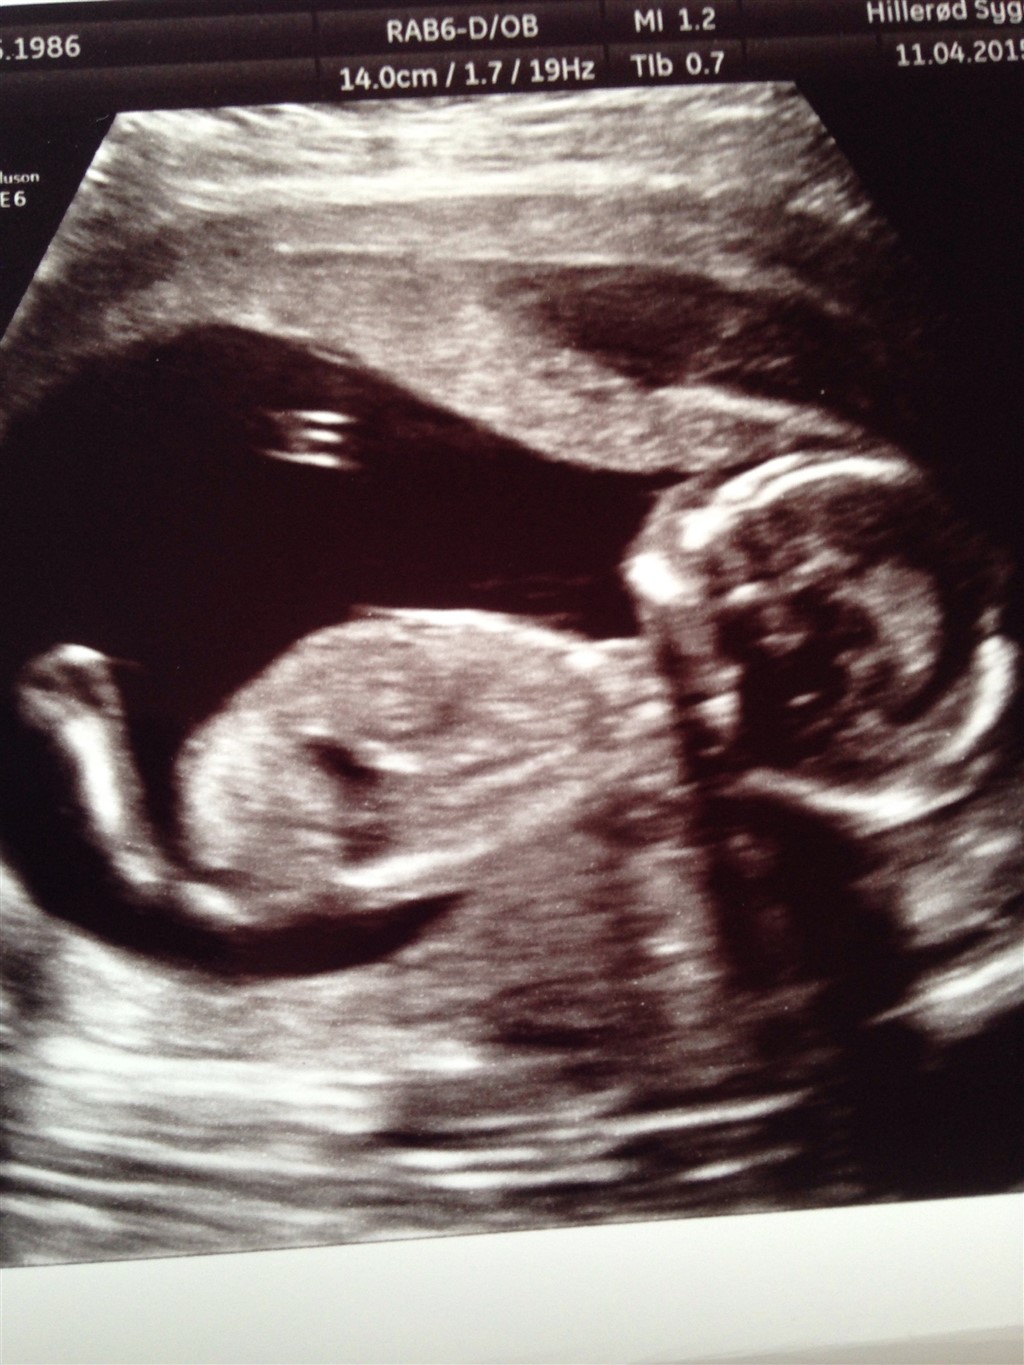

Hvordan går det med jer alle? Her går det fint. Jeg venter på md skanning om 4 uger. Jeg er begyndt at have lidt ondt i ryggen på jobbet, ellers mærker jeg ikke rigtigt noget til det udover maven bare vokser, men ser stadig bare tyk ud

jeg er 16+1 I dag og termin 15/10